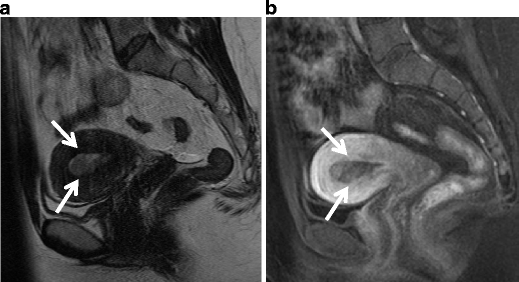

Endometrial stromal sarcoma in a 47-year-old woman. a Sagittal T2-weighted image demonstrates an ill-defined lesion of slightly increased intensity in the posterior myometrium of the uterus (arrows). Note the bands of low signal intensity within the lesion, which represent preserved myometrial bundles amidst the infiltrating nests of tumors cells. b Fusion image with DWI onto T2-weighted image reveals increased signal corresponding to the infiltration tumor in the myometrium